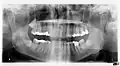

Ортопантомография

Ортопантомография (от греч.: orthos — прямой, правильный, pan — всё, tomos — ломоть, отрезанный кусок и grapho — писать, рисовать) — особый вид рентгеновской съёмки костей лицевого скелета, при котором они «развёртываются» в одну плоскость[1]. Другими словами, рентгенологическое исследование в стоматологии, челюстно-лицевой хирургии, косметологии, позволяющее получать развёрнутое изображение всех зубов с челюстями, прилежащими отделами лицевого скелета. Является первичным рентгенологическим исследованием[2].

Панорамная рентгенограмма показывает нижние зубы мудрости с горизонтальным ретинированием